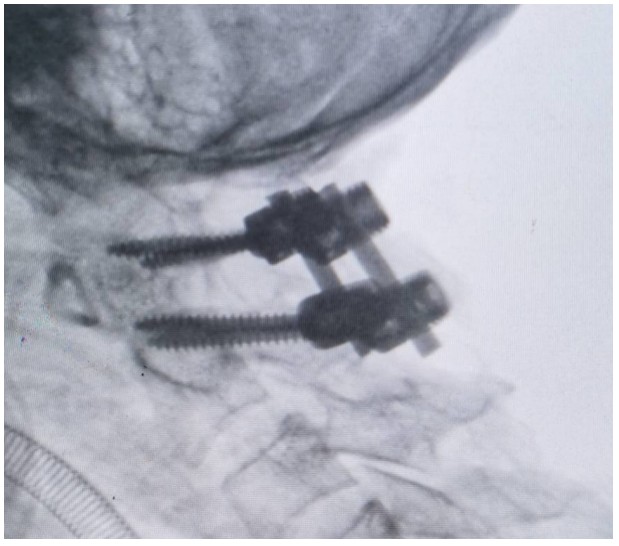

國慶節(jié)前一天,譚女士不幸被門框砸傷頸部,劇烈的疼痛和頸椎的活動受限讓她的世界瞬間陷入了黑暗。在經(jīng)歷了初步的檢查后,譚女士被診斷為寰椎骨折,這個診斷如同一道晴天霹靂,讓她和家人的心沉入了谷底。絕望中,譚女士被緊急轉(zhuǎn)至衡陽市中心醫(yī)院骨科一區(qū)(脊柱外科),錢軍博士及其團(tuán)隊在接到這一緊急病例后迅速接診,經(jīng)過細(xì)致的病史詢問、體格檢查和影像學(xué)資料分析,確診譚女士的寰椎骨折伴有寰樞椎體不穩(wěn)定,迫切需要手術(shù)治療以恢復(fù)其穩(wěn)定性??紤]到上頸椎手術(shù)的高風(fēng)險性,特別是寰樞椎周圍結(jié)構(gòu)復(fù)雜,緊鄰椎動脈和脊髓,手術(shù)過程中的任何微小失誤都可能導(dǎo)致災(zāi)難性后果,錢軍博士團(tuán)隊頂著壓力,迎難而上,沒有絲毫猶豫,立即行急診手術(shù),投入到緊張的救治工作中。

術(shù)中,錢軍博士團(tuán)隊展現(xiàn)出了非凡的勇氣和精湛的醫(yī)術(shù)。他們精心準(zhǔn)備,與手術(shù)室和麻醉科的同仁們緊密協(xié)作,以專業(yè)的技術(shù)和精確的操作,成功完成了這一高難度的手術(shù)。手術(shù)室外,譚女士的家人焦急等待,當(dāng)手術(shù)成功的消息傳來時,譚女士的家人不禁流下了感激的淚水。